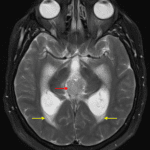

MRI

- Pineal region mass measuring 3.3 x 2.5 x 2.5 cm

- Diffuse intermediate T2 signal, restricted diffusion, and avid enhancement

- Peripheral foci of susceptibility artifact corresponding to calcification on the CT

- Downward mass effect on the tectum with obstructive hydrocephalus at the level of the cerebral aqueduct and subependymal edema